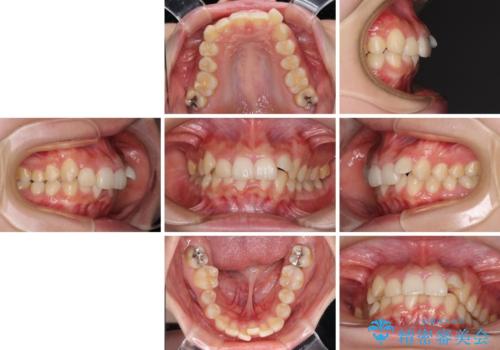

下顎前歯が隠れて突出した口元 ワイヤー装置での抜歯矯正

- 前歯のデコボコと口元の突出感を気にして来院された患者様です。

下顎骨の左右差や、上顎骨の前方位などが認められたため、上下左右の第1小臼歯4本を抜歯し、ワイヤー装置にて矯正治療を行うこととしました。

骨格的な左右差がありましたが、何とか当初予定していた期間で、左右対称の咬み合わせに仕上げることができました。